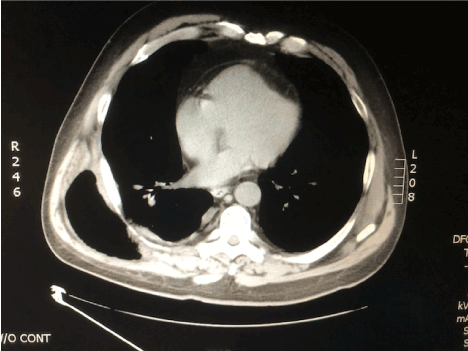

A chest x-ray showed an indistinct right basilar density with a potential small effusion possibly related to atelectasis or pneumonia (Figures 1A and 1B). There were no evident rib fractures.  While preparing for a chest CT, the patient coughed, and the bulge recurred.  CT images showed a large herniation of the right lower lobe between the 9th and 10th rib interspace. The adjacent ribs were separated with interruption of the associated intercostal muscles (Figures 2A and 2B, Figure 3 and Figure 4).

Figure 2A.  CT of chest, non-contrast, mediastinal windows.  Axial view shows a large herniation of the right lower lobe between the eighth and ninth rib interspace and a chest wall defect. The intercostal muscles in this posterior lateral location are discontinuous over a broad area.